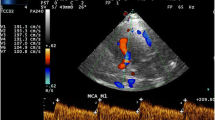

Among the more than 4,000 TCD studies in STOP, more than 250 were abnormal. The qualifying, or highest, velocity was found in the MCA, usually at 46–50 mm depth, in about 85% of cases; it was found in the dICA in about 12% of cases, and in the rest it was found either in the bifurcation area or the more distal segments of the MCA (Fig. 2).

A 9-year-old child with SCD. a TCD demonstrates abnormal right MCA time-average maximum mean velocities measuring over 240 cm/s and a peak systolic velocity of 300 cm/s. b Coronally reconstructed anterior circulation from 3-D time-of-flight MRA demonstrates marked narrowing of the right MCA as well as some narrowing of the right proximal ACA